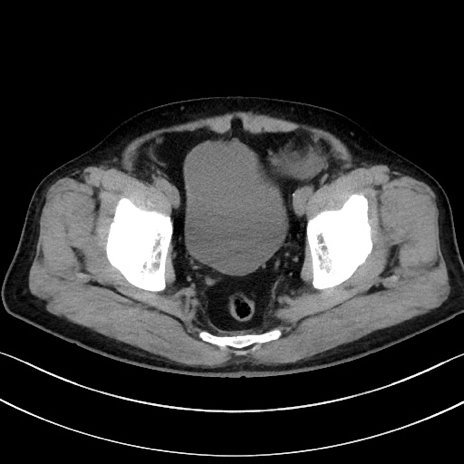

冠状断像

【症例】70歳代男性

【主訴】腹痛

【現病歴】今朝から腹痛あり。全体的に痛い。特に左上の方。排ガスが今日はない。冷や汗が出る。

【既往歴】直腸癌術後

【身体所見】左側腹部〜上腹部に圧痛あり。腹膜刺激症状明らかなではない。軽度反跳痛。左下腹部に術後瘢痕あり。

【データ】WBC 7700、CRP 0.02